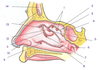

A

Anterior superior alveolar nerve

B

Infra-orbital nerve

C

Pterygopalatine nerves

D

Maxiallary nerve (CN V2) in foramen rotundum

E

Nerve of pterygoid canal

F

Pterygopalatine ganglion

G

Grteater and lesser palatine nerves

H

Posterior superior alveolar nerves

I

Superior dental plexus

1

Infraorbital nerve

2

Ganglionic branches

3

Pterygopalatine ganglion

4

Greater petrosal nerve

5

Deep petrosal nerve

6

Pharyngeal nerve

7

Internal carotid plexus

8

Internal carotid artery

9

Lesser palatine nerve

10

Superior alveolar nn., posterior superior alveolar branches

11

Inferior orbital fissure

12

Greater palatine nerve

13

Medial and lateral superior and posterior inferior nasal branches from nasopalatine n. (V2)

14

Zygomatic nerve

15

Orbital branches (V2)

16

Maxillary nerve (V2)

17

Medial and lateral superior and posterior inferior nasal branches from nasopalatine (V2)